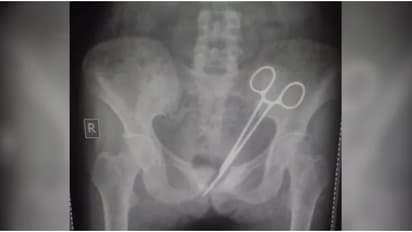

അവിടെ എക്സ്-റേ എടുത്ത് നോക്കിയപ്പോഴാണ് വയറ്റില് ശസ്ത്രക്രിയാ കത്രിക കണ്ടെത്തിയത്. മെഡിക്കൽ വിദഗ്ധരുടെ സംഘം ഉടൻ തന്നെ ശസ്ത്രക്രിയ നടത്തി കത്രിക നീക്കം ചെയ്യുകയും യുവതി സുഖം പ്രാപിക്കുകയും ചെയ്തു. എന്നാല് വാര്ത്ത പ്രചരിച്ചതോടെ സംസ്ഥാനമാകെ കടുത്ത വിമര്ശനങ്ങളുയര്ന്നു. ഇതോടെ സംഭവത്തിൽ അന്വേഷണം ആരംഭിച്ചിട്ടുണ്ട്.